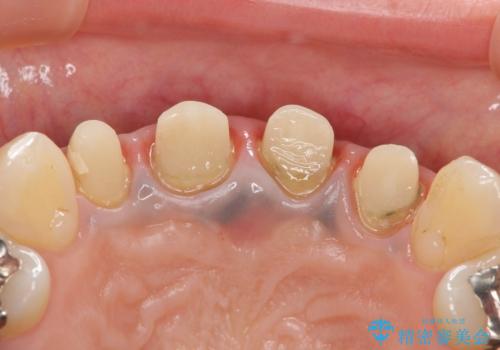

金属を用いたコア・クラウンが装着されており、全ての金属を除去したのちのメタルフリー治療を計画します。

ファイバーコア・セラミッククラウンは金属を用いない審美的な治療法です。